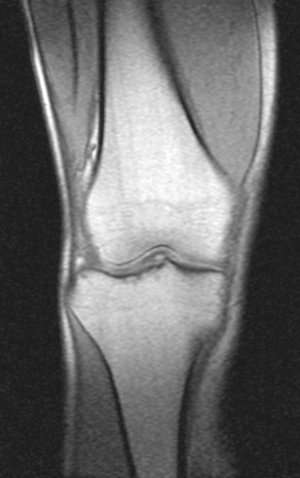

Недавно,5 сентября получил травму на работе. Выходя из транспорта почувствовал резкую боль с внутренней стороны колена (как бы ножом режет). Весь день не мог нормально поднять ногу. Особенно боль проявлялась при спуске по ступенькам. Через 3 часа после травмы обратился в травмпункт. Там сделали рентгенный снимок и сказали, что все впорядке. На следующий день весь коленный сустав с внешней стороны стал как бы после заморозки (холодить изнутри). Через дней 5-6 боль притупилась, а еще через несколько дней прошла. Но сустав все еще морозит изнутри. При резких движениях ощущения что кости сустава выходят и входят обратно на свое место. И сустав как будто чугунный. 8 октября сделал МРТ (так как большие очереди пришлось месяц прождать). Врач делавший МРТ сказал что дислокация коленной чашечки. К травмотологу только через неделю записан. Может подскажите что это? И последнее, сегодня начал морозить изнутри и сустав другой ноги. И холодок теперь идет от колена и вниз аж до пальцев на обеих ногах. Как бы онимения. Теперь не могу пробежать и нескольких метров такое ощущения что ниже колена мышцы как деревянные. Вот некоторые снимки МРТ. Рентген будет завтра на руках, если понадобится. Есть ли на самом деле смещение коленной чашечки?